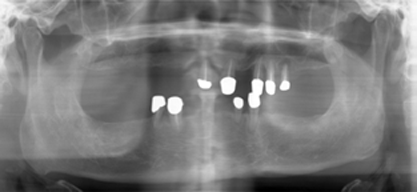

Fig.2

Mr. Fan is 65 years old.  He has had upper and lower overdentures for ten years. Both of them are loose.  He also complains pain associated with upper distal abutments: #8 and 13.  Exam shows generalized advanced chronic periodontits (Fig.1, 2 (upper anterior PAs), 3 (lower anterior PAs).  All of the remaining teeth are nonsalvageable.  The width of the alveolar ridges is adequate (Fig.4 and 7).  The ridge height of the mandible is sufficient, whereas that of the maxilla is questionable (Fig.1).  The patient prefers fixed prosthetics.  We plan to place as many as 24 implants in stages.